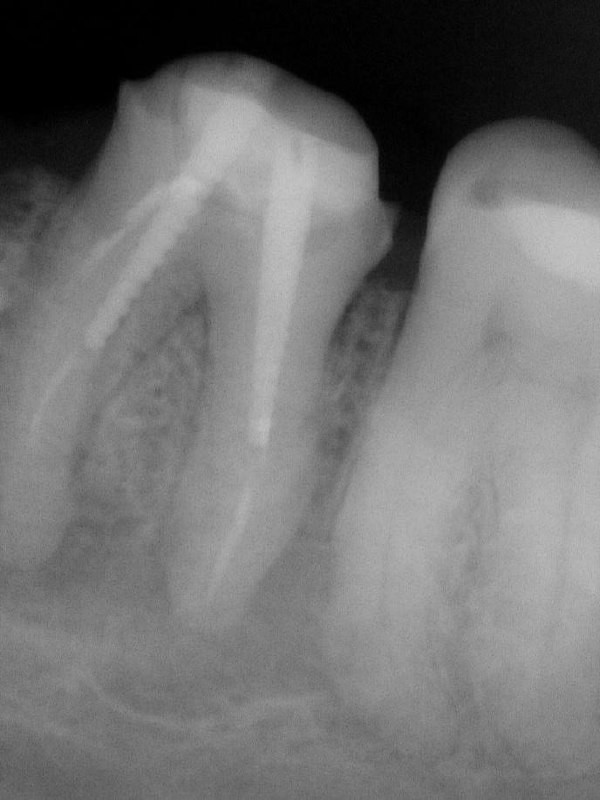

- 🌶️ Полезная информация про резорбции - изучать по #резорбции@dr_dobriyan